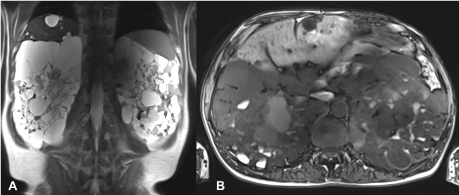

MR imaging of the abdomen was performed, showing multiple renal cysts on both sides. Some of the cysts also showed high protein or hemorrhagic shares. In addition, multiple liver parenchyma cysts and a diverticulosis coli were described (Figure 1).

Figure 1. Initial MR examination: T2-weighted HASTE in coronal (a) and T1-weighted VIBE in transverse (b) orientation show multiple renal cysts with partial high protein or hemorrhagic content and multiple liver parenchyma cysts.